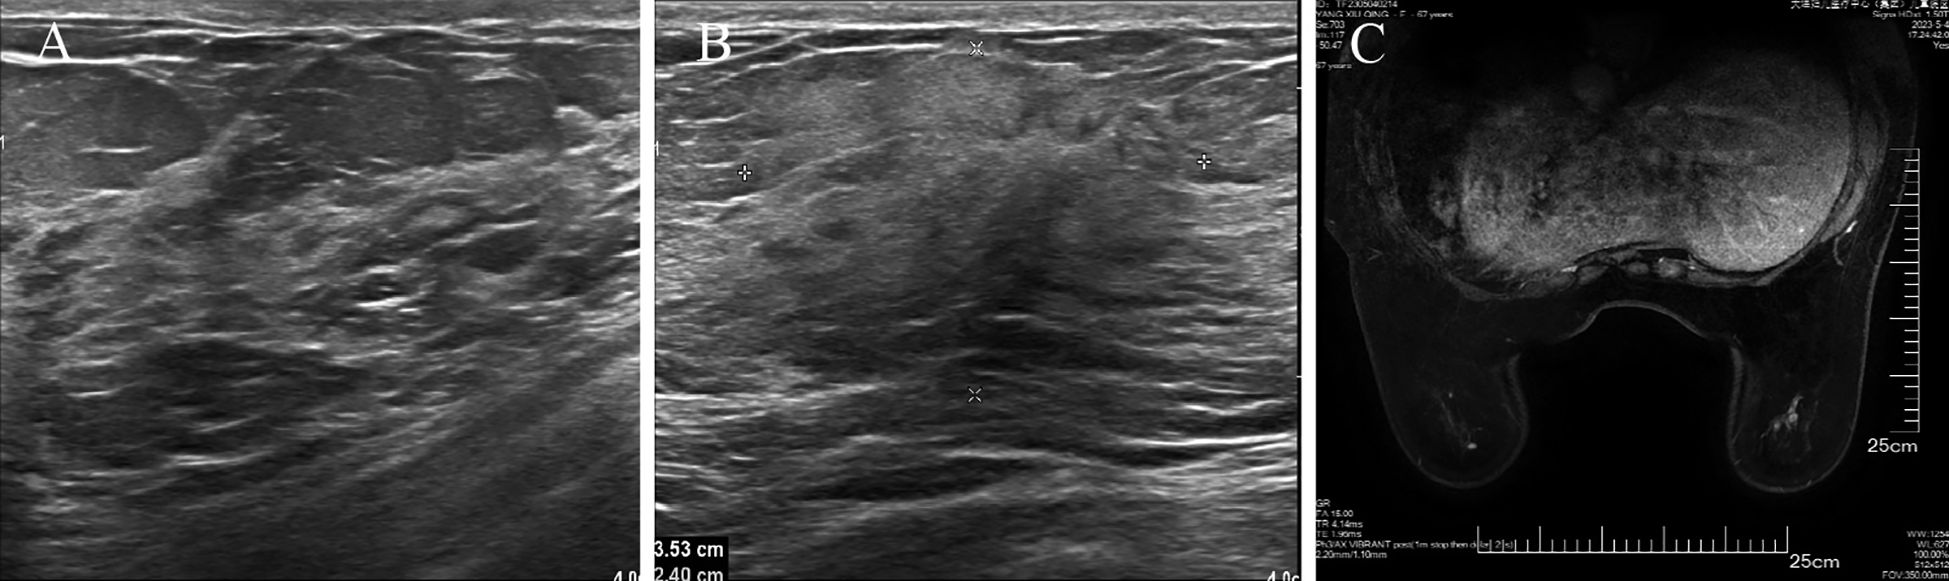

The patient underwent a secondary procedure to ensure negative margins. Preoperative ultrasound of the right breast showed slightly enhanced localized echogenicity at 7–9 o’clock, with a size of 3.5×3.2×2.4 cm, unclear borders, irregular morphology, no obvious blood flow signal on color Doppler flow imaging, and no obvious enlargement of lymph nodes in both axillae (Figures 1A, B). Contrast-enhanced magnetic resonance imaging (MRI) scan of the breast showed multiple scattered small nodular foci of significant enhancement in the right breast, with most of the lesions having a diameter of 2–3 mm and clear and smooth borders. One of the lesions was larger (diameter about 6mm) and located in the outer and lower quadrant, having a smooth border, with time-signal intensity curve (TIC) of the plateau pattern and significant enhancement of the ductal region seen beside it. The upper edge of the skin of the right breast was not smooth, and the reconstruction image showed a rounded area of slightly high signal intensity (Figure 1C). The right breast mass was then excised, and the upper, lower, inner, and outer margins of the excised tissue were collected and sent for examination. During the operation, and a bulky piece of breast tissue was seen, with size 7.5 × 6 × 1.7cm, and a grayish-yellow area was seen at the marking place, 0.8 × 0.6 × 0.5cm, with medium texture. The remaining breast tissue appeared grayish white, interspersed with areas of grayish yellow and was soft in texture. No cancerous tissue was seen at the margins of the excised breast tissue (upper, lower, inner, or outer). The tumor cells were arranged in a multinodular, solid, papillary arrangement, while the tumor cells themselves were hypercolumnar cytoplasmic, eosinophilic, and rich in mitochondria. Dispersed in the nodules were single round to oval mesonuclear grade cells. The oval nucleus showed invaginations of the nuclear membrane parallel to the long axis of the nucleus or a nuclear furrow with folded nuclear membrane, and the nuclear furrow invagination was encapsulated into the cytoplasm as intranuclear pseudo-inclusion bodies (Figures 2A1-3). The results of immunohistochemistry were as follows: ER (-), PR (-), HER-2 (-), Ki-67 (+ about 10%), AR (-), CK5/6 (+), CK7 (+), P63 (-), Calponin (-), SIA (-), SMMHC (-), GCDFP-15 (-), GATA-3 (-), TTF1 (-), CD68 (histiocyte+), CD163 (histiocyte+) (Figures 2B–E). On the basis of the investigative results, the patient was treated with local radiotherapy of the right breast after surgery, with planning target volume of 50Gy/25Fx (Figures 3A–D, Table 1). Dose Volume Histogram (DVH) shows, for any given point on a curve, the corresponding dose (X-value) and volume (Y-value) can be determined. For example, the CTV (Clinical Target Volume) curve shows that 100% of the volume received at least 36 Gy, and 95% of the volume (as per our planning goal) received the prescribed dose of 50 Gy. Steep curves (e.g., CTV) are ideal for target volumes, indicating a homogeneous dose with a sharp fall-off outside the target. Gradual curves (e.g., Lung-R) are typical for OARs(Off-Axis Ratio), showing that a gradient of doses is delivered across the organ. No acute adverse events of grade 2 or higher (according to CTCAE v5.0 criteria) during the radiotherapy was found. The patient was scheduled for periodic follow-up. This comprehensive surveillance strategy encompassed serial tumor marker evaluation (CEA, CA 125, CA 15-3), breast and abdominal ultrasonography, with the former including detailed inspection of the axillary, supraclavicular, and infraclavicular lymph nodes. Cross-sectional imaging via CT was utilized for the chest and head, supplemented by whole-body bone scintigraphy to screen for osseous metastases. Every 3 months for the first year, every 6 months for the second year and then annually thereafter. At the most recent follow-up visit in Aug, 2025 (approximately 24 months post-treatment), the patient remained asymptomatic with no clinical or radiological evidence of local recurrence or distant metastasis. The detailed timeline of key events related to the disease has been showed in Table 2. The resected cancer tissue was subjected to next-generation sequencing (NGS) using a GENESEEQPRIME® pan-cancer panel covering approximately 1.5 Mb of the coding regions of over 400 genes (including exons, fusion-associated introns, variable shear regions, and specific microsatellite (MS) locus regions of more than 400 genes related to tumor targeting, diagnosis, prognosis, and tumor development). The TMB was calculated as 2.1 mutations/Mb, which is classified as TMB-Low based on the established cut-off of ≥ft mut/Mb for panels of this size. The results of NGS revealed that our patient had a missense mutation in exon 20 of the p.H1047R (PIK3CA), with a mutation abundance of 25.00%, and p.R172T exon 4 missense mutation in IDH2, with a mutation abundance of 21.91%. Additionally, 2.1 mutations/Mb, indicating a low tumor mutational burden (TMB), sorted in the top 84.59% were noted (Figures 4A–C). The mutational sites of enzymes related to polymorphisms in drug metabolism are as follows: ERCC2 gene polymorphic mutation, XRCC1 Q399R pure-sum mutation, UGT1A1 polymorphic mutation, TYMS-6bp/-6bo polymorphic mutation, CYP2B6 gene pure-sum polymorphic mutation, and NQO1 gene polymorphic mutationality (Table 3). Mineralocorticoid receptor (MR)-related genes and MS-high (MSI-H) were not detected, and HLA-I typing was determined to be partially pure-sum (Table 4).

Medical imaging of a chest region is divided into four panels and a graph. Panels A, C, and D are cross-sectional views showing color-coded areas, likely representing radiation dosage or areas of interest, with different opacity levels. Panel B shows a volumetric rendering with highlighted sections. The graph (E) displays a dose-volume histogram with multiple lines indicating various dose levels and corresponding volume percentages. The x-axis represents the dose in cGrays (cGy), and the y-axis represents volume percentage.

Figure 3. Radiotherapy target area outlining in TCCRP. (A-D) Radiation Treatment Target Delineation Image shows the target areas of tumor and normal tissues. (E) Total Volume DVH (DVH, Dose Volume Histogram) shows the distribution of radiation doses received by target areas of tumor and normal tissues. The DVH is a graphical representation of the radiation dose distribution delivered to the target volumes and critical organs at risk (OARs). The X-axis represents the radiation dose (in Gy). The Y-axis represents the volume of the structure (as a percentage) that receives at least the corresponding dose on the X-axis.